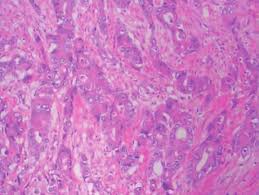

Webpathology Com A Collection Of Surgical Pathology Images

Webpathology Com A Collection Of Surgical Pathology Images from www.webpathology.com

In a cursory evaluation, this tumor can be easily confused for a benign fibrous pleurisy. Van kaick g, dalheimer a, hornik s, et al. Epithelioid mesothelioma cells spread more slowly than sarcomatoid cancer cells. Pleural mesothelioma most common type. Pathology reports from 1997 to 2006 were reviewed at two academic institutions to identify patients with proven pleural mesothelioma.